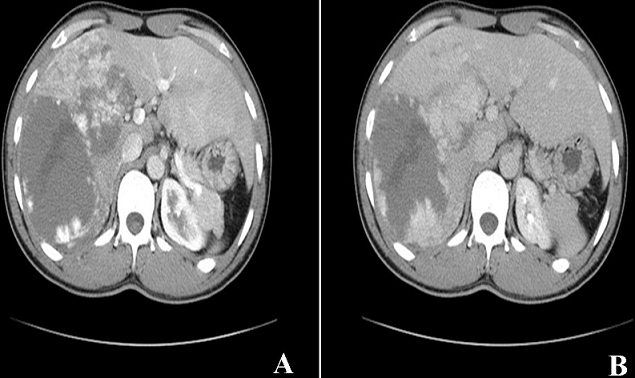

Les angiomes hépatiques sont des tumeurs bénignes du foie les plus fréquentes. Ils touchent tous les âges mais souvent des adultes avec une prédominance féminine. Souvent la lésion est unique de taille inférieure à 1 cm dans la moitié des cas. Elle peut être double ou multiple dans certains cas.Nous rapportons l'observation d'un patient de 40 ans sans antécédent notable qui présente depuis une semaine des douleurs isolées de l'hypochondre droit. L'examen clinique trouve un patient en bon état général avec une légère sensibilité de l'hypochondre droit. L'échographie abdominale est revenue en faveur d'un foie augmenté de taille de contours réguliers et d'échostructure hétérogène, siège d'une lésion nodulaire au niveau du segment VI et VII de 86 mm de grand axe. Le scanner abdominal montre un foie augmenté de taille de contours réguliers et de densité homogène, siège d'une volumineuse masse hypodense à centre liquidien, occupant tout le foie droit, mesurant 17 x 9 cm avec un rehaussement discontinu périphérique en motte au temps artériel (A) et un remplissage progressif et centripète aux temps portal et tardif (B).